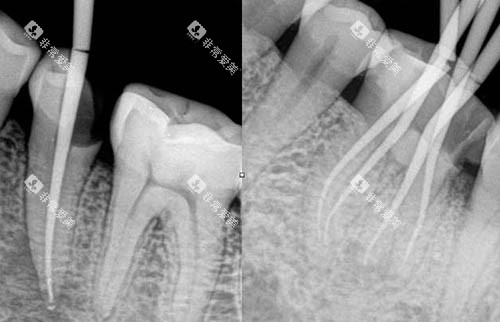

根管治疗主要用于治疗牙髓炎、根尖周炎等牙齿疾病。

在河北医科大学第三医院,根管治疗的费用主要与牙齿的部位有关。

前牙根管治疗

前牙的根管结构相对简单,治疗难度较小,费用一般在300 - 800元左右。

前磨牙根管治疗

前磨牙的根管数量和复杂程度介于前牙和磨牙之间,根管治疗费用大约在500 - 1200元左右。

磨牙根管治疗

磨牙的根管系统较为复杂,通常有多个根管,治疗难度较大,费用相对较高,一般在800 - 2000元左右。